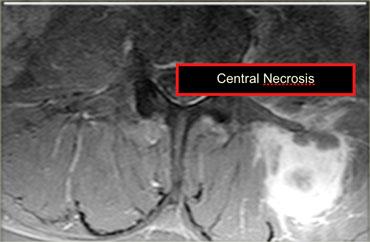

Bên trái là hình ảnh di căn của ung thư biểu mô tế bào thận.

Khi nghi ngờ, hãy sử dụng gadolinium để xem liệu tổn thương có ngấm thuốc hay không.

Tiếp tục với hình ảnh sau tiêm Gad.

Phần lớn tổn thương ngấm thuốc, khiến khả năng tụ máu khó xảy ra.

Ở trung tâm không có sự ngấm thuốc do hoại tử.

Tụ máu có thể có một số ngấm thuốc, nhưng chỉ ở rìa.